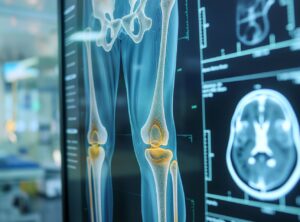

Uso do robô para fazer prótese de joelho: tudo o que você precisa saber

A cirurgia de prótese de joelho evoluiu muito nos últimos anos. Entre essas evoluções, o uso de robô se tornou uma das principais novidades na